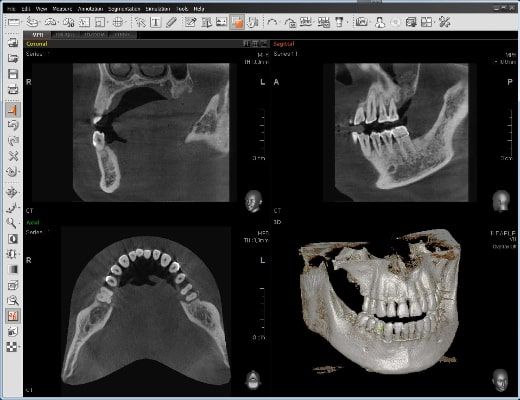

El innovador FOV proporciona un volumen en forma de arco que muestra una vista más amplia de la dentición en comparación con otros dispositivos del mismo FOV.

Normalmente, una imagen de 10x8.5 muestra el diente No.8. Sin embargo, cuando los terceros molares están tumbados sobre su lado hay una gran posibilidad de que el diente se corte de la imagen.

El “volumen en forma de arco” elimina esta posibilidad y muestra el área de dentición oculto.